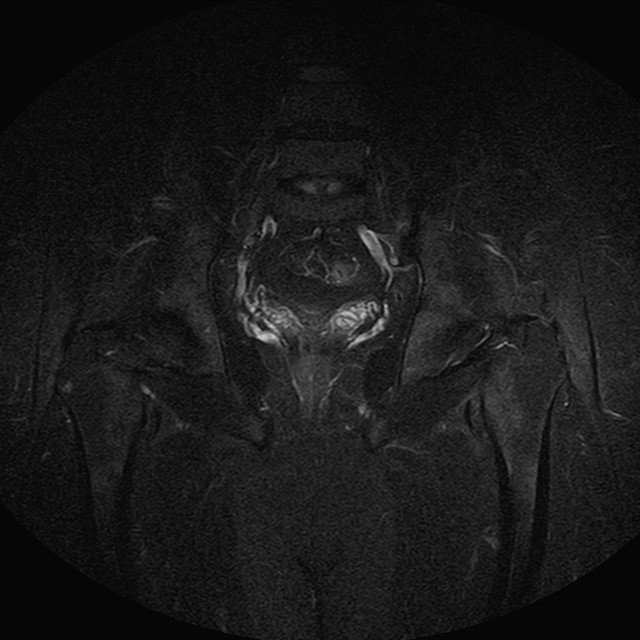

Esami: RMN BACINO

Evidenti e simmetriche alterazioni osteofitosiche in regione coxo femorale con riduzione delle rime articolari. Degenerazione completa del cercine glenoideo. Non attuali segni di versamento articolare. Non segni di edema osseo che escludono attuale algodistrofia od osteonecrosi. Lieve e simmetrica riduzione del trofismo della muscolatura glutea.